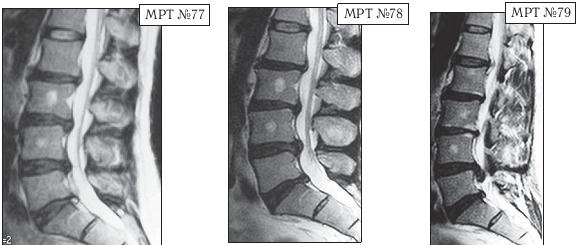

Следующий пример в продолжение нашей темы, как пациент поддался рекламе и обратился к мануальному терапевту, который гарантировал «полное избавление от болей». Данный пациент по профессии строитель. Испытывал периодические боли в поясничном отделе позвоночника с 1996 года. Неоднократно проходил медикаментозное лечение под наблюдением невропатолога. Диагностические обследования позвоночника в этот период лечения не проводились. В августе 2002 года во время санаторно-курортного лечения, по назначению лечащего врача, прошёл курс вытяжения позвоночника, после которого началось обострение, появилась боль и онемение в правой ноге. Во время стационарного лечения в неврологическом отделении провели МРТ-обследования (МРТ № 80) и порекомендовали проконсультироваться у нейрохирурга. Пациент проконсультировался у нейрохирурга, но от предложенной операции отказался. Под контролем специалистов лечился медикаментозно. В марте 2010 года, соблазнившись рекламой, данный пациент решил «навсегда избавится от болей в позвоночнике» и обратился к мануальному терапевту, который гарантировал «полное избавление от болей». Результатом этого «гарантированного лечения» (результат отображен на МРТ № 82) стала секвестрированная грыжа межпозвонкового диска и, естественно, значительное ухудшение самочувствия данного пациента.

Иллюстрация к книге — Остеохондроз для профессионального пациента [i_110.jpg]

На МРТ № 80 от 04.09.2002 года, наблюдается исправление физиологического лордоза, грыжа межпозвонкового диска в сегменте LIV—LV, стеноз спинномозгового канала на данном уровне, компенсированная спондилёзом протрузия в сегменте LV—SI

На МРТ № 81 того же пациента от 19.07.2007 наблюдается практически аналогичная с 2002 годом картина, с той лишь разницей, что грыжа межпозвонкового диска в сегменте LIv-Lv частично компенсировалась спондилёзом.

На МРТ № 82 того же пациента от 02.04.2010 наблюдается исправление физиологического лордоза, компенсированная спондилёзом грыжа межпозвонкового диска в сегменте LIV-LV, секвестрированная грыжа межпозвонкового диска в сегменте LV—SI абсолютный стеноз спинномозгового канала на данных уровнях.

На увеличенных фрагментах (МРТ № 83, МРТ № 84,МРТ № 85) наблюдается сегмент LIV-LV, на котором видно, как грыжа межпозвонкового диска компенсируется спондилёзом (обрастает костными наростами, исходящими из тел позвонков). При этом заметьте, грыжа сохраняет свои границы, что даже при визуальном сравнении отчетливо наблюдается по стенозу спинномозгового канала на данном уровне (отмечено стрелочками). Это ещё один пример того, как грыжи межпозвонкового диска могут, по выражению мануальных терапевтов, «уходить» сами по себе. Несмотря на то, что грыжа межпозвонкового диска у данного пациента компенсировалась спондилёзом, но стеноз спинномозгового канала от этого не уменьшился и самочувствие не улучшилось.

Так что если вы увидите многообещающую рекламу, в которой говориться, что специалисты занимаются безоперационным лечением грыж, то надо понимать, что лечением-то они занимаются, но вылечивают ли? Это вопрос. А для того чтобы убедиться в искренности намерений специалистов подобных медицинских центров, необходимо прежде всего ознакомится не только с отзывами о субъективных ощущениях их пациентов, но и с объективными результатами обследования, зафиксированными на МРТ-снимках, к примеру до и после лечения их пациентов с аналогичными заболеваниями, а также, по возможности, результатами отдаленных последствий такого лечения.